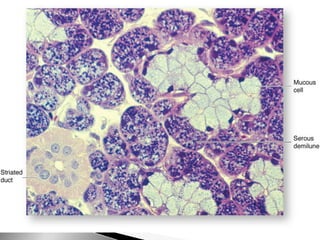

Glándulas